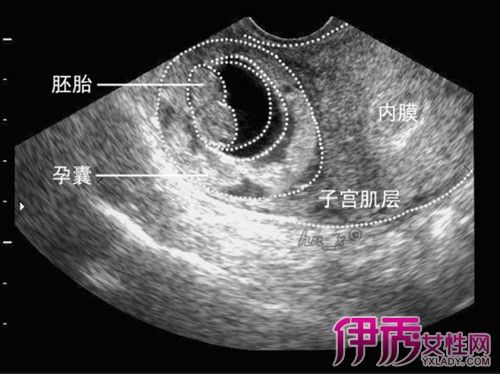

促排卵怀孕的孩子健康吗

促排卵是指利用药物促进卵泡发育,并结合过多的雌激素和黄体酮,以提高卵泡的质量。因为怀孕后来雌孕激素过多是由卵巢来促使的。正常的情况下,女性整个卵巢在卵泡期会形成一个黄的雄状,排卵结束之后形成黄的骨骼睾丸以及性腺。一个成熟的睾丸需要三到七天的时候形成睾丸,生殖器官出生后仍会有正常的精子。